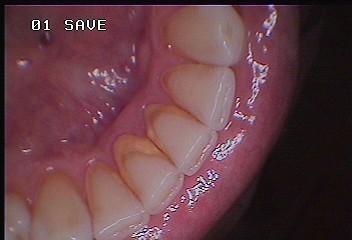

O caso da foto é de um homem de 40 anos que faz boa higiene, escovando corretamente três vezes ao dia e utiliza o fio dental. Num diagnóstico tradicional, sem utilização da câmera intra oral com certeza o cirurgião dentista indicaria uma raspagem de tártaro e profilaxia preventiva, incluindo regularização e polimento de restaurações de resina composta, eliminando pequenos degraus que facilitam o acúmulo de placa bacteriana e consequentemente formação de tártaro.Como o paciente não costuma ter qualquer outro problema na boca, muitas vezes é difícil convencê-lo da necessidade do tratamento utilizando apenas espelhos.

Nessa hora a câmera intra oral mostra a importância da tecnologia. O paciente fica surpreso e quase não acredita no que está vendo autorizando o procedimento imediatamente.